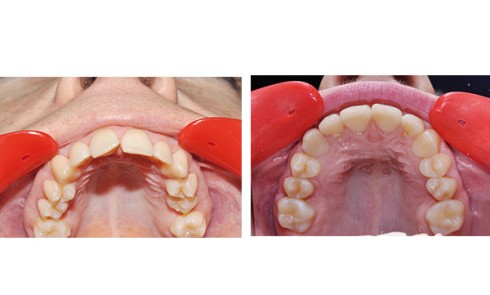

La patiente est une adulte de 22 ans présentant une rétrognathie mandibulaire associée à une endoalvéolie mandibulaire avec un défaut...